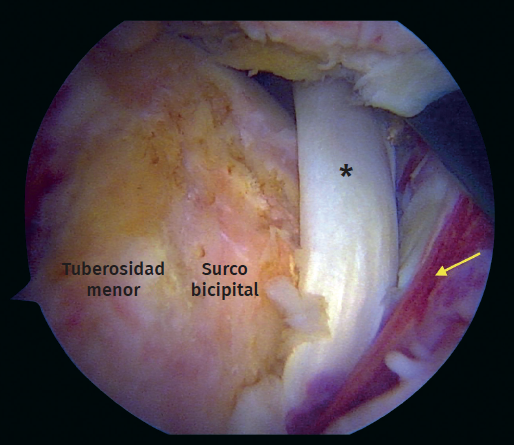

Durante el periodo descrito, se intervino a un total de 15 pacientes que cumplían con los criterios de inclusión. Se excluyó a un paciente debido a que el tiempo de seguimiento era insuficiente. Se incluyeron un total de 14 pacientes (Tabla 1), con una edad promedio de 65 años (rango de 46 a 76 años), 8 de los cuales eran hombres (57%). El tiempo promedio de seguimiento fue de 29,4 meses (rango de 24 a 41 meses). De los 14 pacientes evaluados, 13 (92,8%) presentaban algún compromiso del bíceps proximal como roturas parciales, lesiones degenerativas o inestabilidad medial (Figura 5). Se realizó una tenotomía del bíceps en 9 pacientes (64,2%), una tenodesis intraarticular en 2 casos (14,2%) y se detectó una rotura crónica del bíceps en 2 pacientes (14,2%). En la mitad de los pacientes (7) la rotura subescapular se reparó con 2 anclajes con nudo y en los restantes, con una fijación híbrida utilizando un anclaje superior con nudo y un anclaje inferior sin nudo con cintas de sutura (Tabla 2).

Figura 5. Vista artroscópica. Rotura completa del subescapular con inestabilidad medial de la cabeza larga del tendón del bíceps. Asterisco: tendón del bíceps. Flecha: rotura del tendón subescapular.